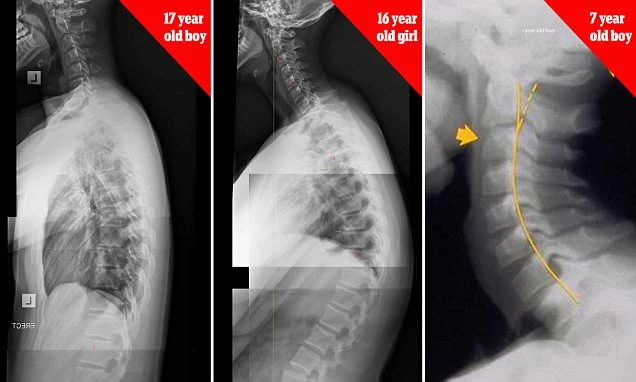

Những hình ảnh chup X-quang cho thấy trẻ em từ 7 tuổi cho đến thanh thiếu niên có xương cổ và cột sống biến dạng nghiêm trọng do suốt ngày chúi mặt vào điện thoại thông minh.

Bác sĩ Carter cảnh báo rằng hiện tượng "text neck" (tạm dịch - cổ nhắn tin) - hậu quả của việc cúi xuống nhìn màn hình quá lâu do nghiện smartphone đang dần trở thành dịch bệnh trong giới trẻ.

Ông chia sẻ: "Đây là một hiện tượng đáng báo động. Theo quan sát của tôi trong những năm qua, số lượng bệnh nhân bị biến dạng cột sống tăng rất mạnh, trong đó 50% là thanh thiếu niên". Khi cột sống thoái hóa, những người này sẽ phải chịu những cơn đau đầu, cổ, vai và lưng.

Theo nghiên cứu của bác sĩ, những người sử dụng smartphone đang dành ít nhất 4 tiếng/ngày nhìn vào màn hình - tức là một năm họ mất đến 1.400 giờ, dẫn đến áp lực kinh khủng lên đốt sống cổ. Cụ thể, khi ta đứng thẳng, cổ sẽ phải chịu một áp lực khoảng 5kg. Tuy nhiên khi cúi xuống, tùy theo góc độ mà áp lực cổ phải chịu tăng dần, dao động trong khoảng 12,2 kg khi cúi 15 độ, đến 27 kg khi cúi 60 độ. Với áp lực khủng khiếp như vậy, lâu dần đốt sống cổ sẽ bị thoái hóa và biến dạng, tạo thành hiện tượng "cổ nhắn tin".